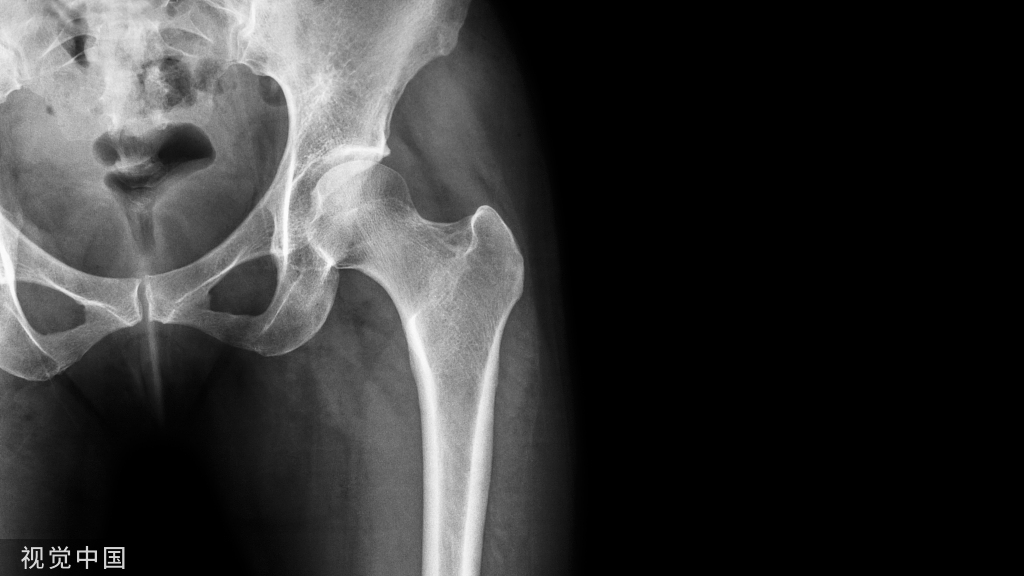

影像学表现

早期

晚期